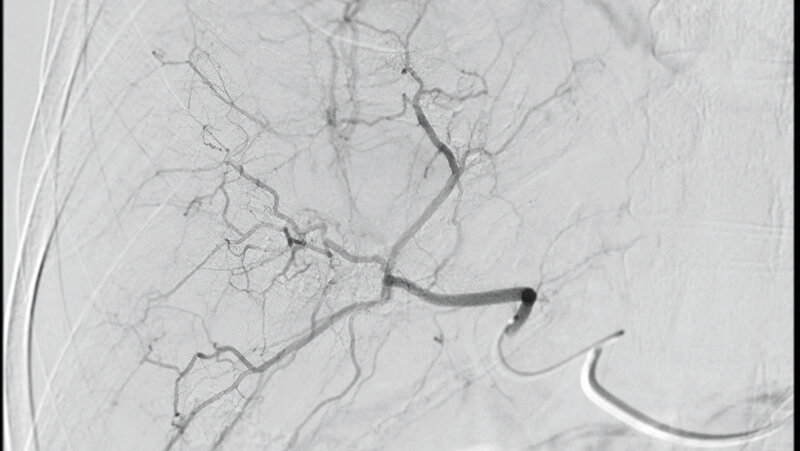

TACE – transarterielle Chemoembolisation der Leber

Die TACE ist eine etablierte interventionelle Behandlung bösartiger Lebertumoren, in erster Linie des HCC. Sie wird durchleuchtungsgesteuert vom Team der Angiografie durchgeführt, wobei MTR verschiedene Aufgaben von der Organisation des Eingriffs über die Patientenbetreuung bis zur sterilen Assistenz übernehmen.